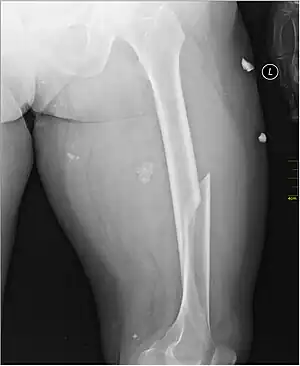

X-ray image of a femoral shaft fracture

A femoral fracture is a bone fracture that involves the femur.[1] They are typically sustained in high-impact trauma, such as car crashes, due to the large amount of force needed to break the bone. Fractures of the diaphysis, or middle of the femur, are managed differently from those at the head, neck, and trochanter